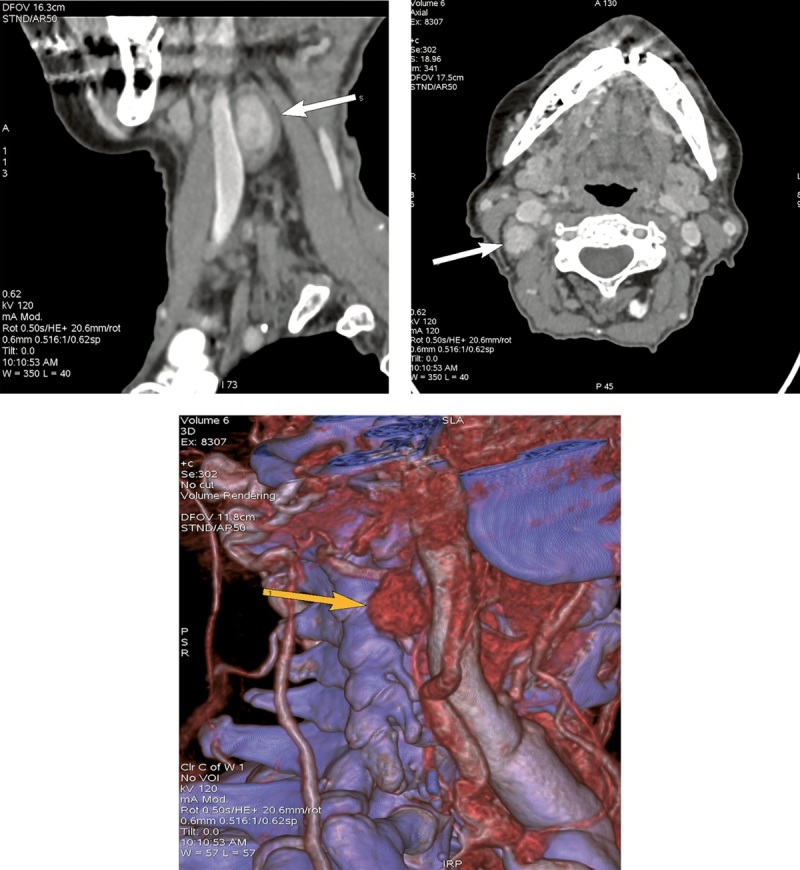

Topical diagnosis can be severely complicated in patients with primary hyperparathyroidism (PHPT) due to the ectopic placement of parathyroid gland (PTG) formations. We report a clinical case of PHPT in an 84-year-old patient caused by ectopic PTG adenoma located behind the right internal jugular vein at the level of the right submandibular gland. The impossibility of surgery for a long time due to the absence of a topical diagnosis has necessitated conservative treatment was required to get the hypercalcemia under control. In view of the concomitant deficiency of vitamin D, an attempt was made to use therapy with saturating doses of cholecalciferol under dynamic monitoring of the indicators of phosphorus-calcium metabolism, which allowed to achieve a significant decrease in PTH levels while maintaining normocalcemia.